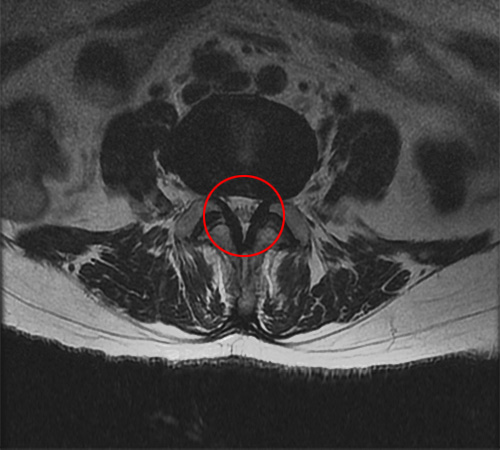

MRI 영상으로 봤을 때는 척추의 퇴행성 변화로 인해 황색인대가 부풀어오르기 시작하는 것을 협착증 초기로 봅니다. 그 다음 척추관 중앙의 공간이 30% 이상 막힌 것을 중기라고 판단하며, 척추관의 공간이 50% 이상 막혀서 심한 보행장애를 동반하는 것을 협착증 말기로 봅니다.